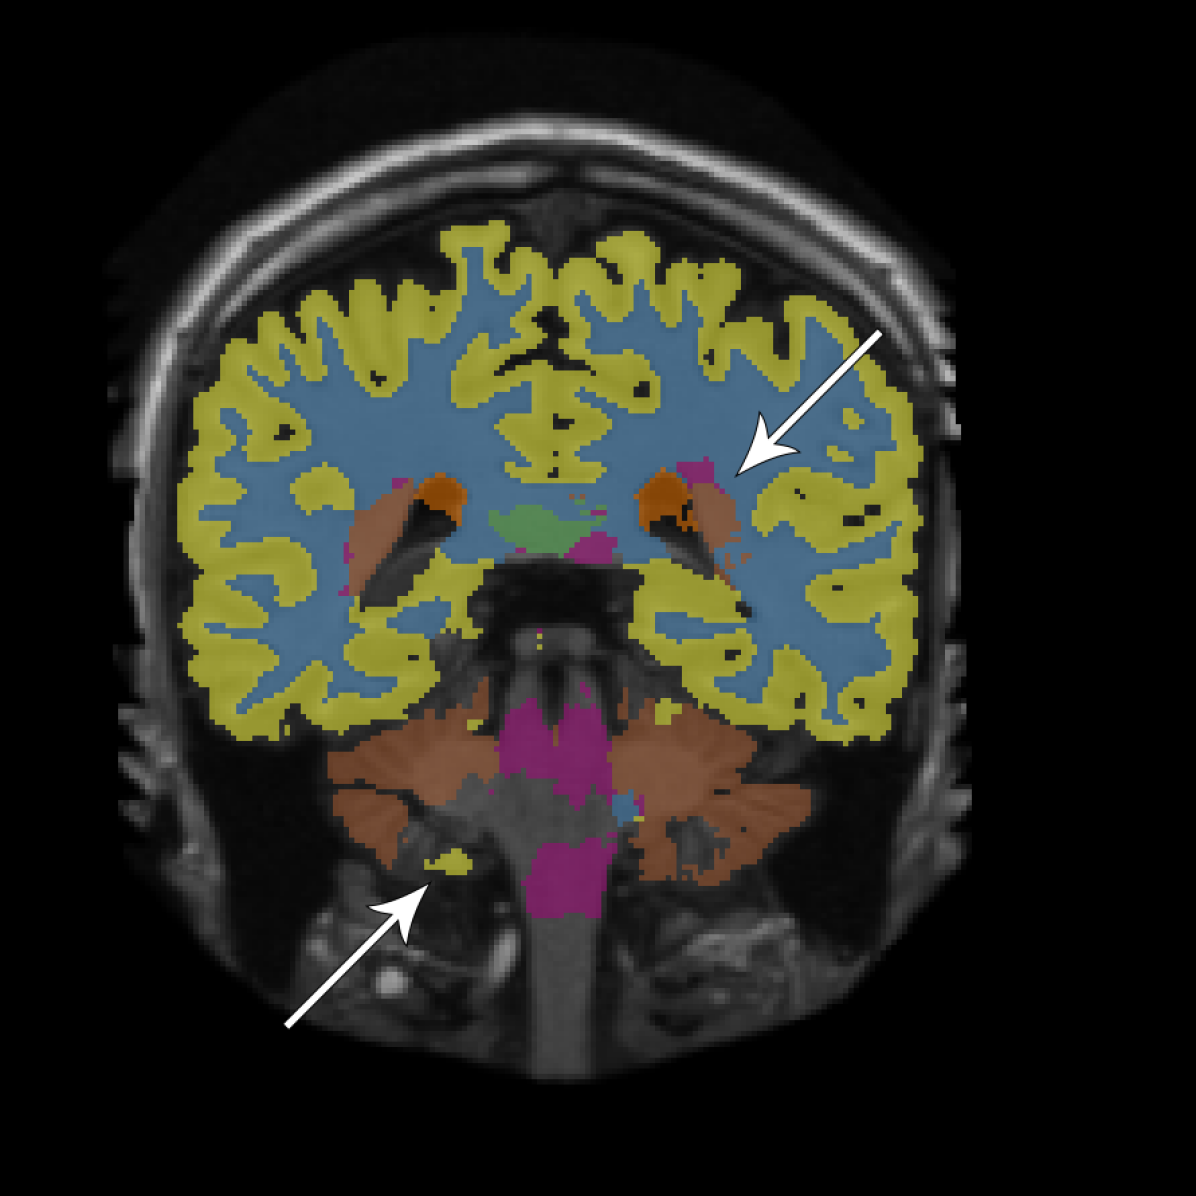

Figure 2 provides a visual comparison between the segmentations obtained with and without adversarial training, showing that the adversarial approach generally resulted in less noisy segmentations. The same can be seen from the total number of 3D components (including the background class) that compose the segmentations. For the adult subjects, the number of components per image () decreased from to using the fully convolutional network and from to using the dilated network. For the elderly subjects, the number of components per image () decreased from to using the fully convolutional network and from to using the dilated network.

We have presented an approach to improve brain MRI segmentation by adversarial training. The results showed improved segmentation performance both qualitatively (Figure 2) and quantitatively in terms of DC (Figure 3). The improvements were especially clear for the deeper, more difficult to train, fully convolutional networks as compared with the more shallow dilated networks. Furthermore, the approach improved structural consistency, e.g. visible from the reduced number of components in the segmentations. Because these improvements were usually small in size, their effect on the DC was limited.